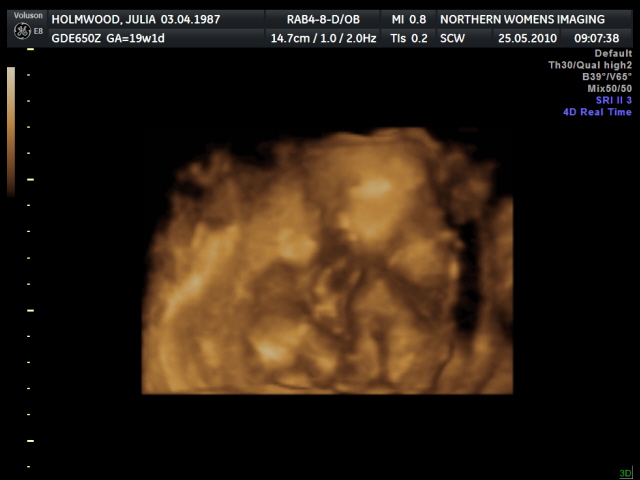

Ultrasound - 19 weeks - Julia - FlickrLos ultrasonidos juegan un papel importante para garantizar el éxito de un embarazo. Los ultrasonidos 4D brindan mayor detalle y calidad de imagen en comparación con 2D o 3D. Se captura el movimiento en tiempo real, lo que permite una mejor observación y evaluación. Con sus numerosos beneficios; no es de extrañar que se esté volviendo más prominente en estos días.

Un escaneo de bebé 4D proporciona una imagen clara, mejor y detallada del bebé. Puede producir una imagen de la cara real del bebé, sus ojos, nariz y boca. Y también puede obtener otras imágenes esenciales, desde rasgos y expresiones faciales hasta órganos internos. Los padres tienen la oportunidad de ver a su bebé sonreír y moverse dentro del útero. Estas imágenes detalladas son importantes para evaluar, medir y observar al bebé.

Además de obtener una imagen increíble del ultrasonido 4D del bebé, ver al bebé moverse dentro del útero ayuda a evaluar sus movimientos. Los ultrasonidos 4D ayudan mucho al permitir que los médicos observen y comenten las actividades del bebé en tiempo real, como bostezar, dormir, patear, chuparse el dedo, parpadear y más. No solo hay imágenes asombrosas de ver, sino que también son una indicación importante de la salud del bebé.